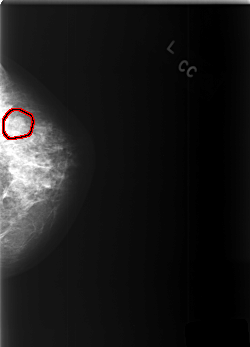

C_0372_1.LEFT_CC

LEFT_CC LINES 5552 PIXELS_PER_LINE 4000 BITS_PER_PIXEL 12 RESOLUTION 50 OVERLAY

FILE: C_0372_1.LEFT_CC.OVERLAY

TOTAL_ABNORMALITIES 1

ABNORMALITY 1

LESION_TYPE MASS SHAPE ROUND MARGINS MICROLOBULATED

ASSESSMENT 3

SUBTLETY 4

PATHOLOGY BENIGN

TOTAL_OUTLINES 1

BOUNDARY